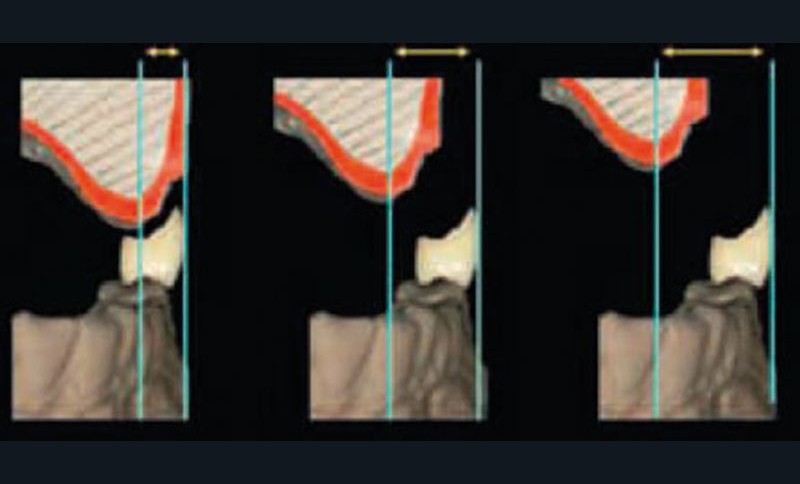

Le choix d’une prothèse amovible complète supra implantaire (PACSI), par opposition à une prothèse fixe implanto-portée, est guidé par différents facteurs. Nous retrouvons en premier lieu le degré de résorption osseuse, le niveau de décalage des bases osseuses, l’espace inter- arcades, la qualité osseuse, le volume osseux disponible, les moyens financiers du patient, et le refus de techniques de chirurgie lourde pour les personnes âgées (fig. 1 et 2).

La prothèse amovible sur implants doit être immédiatement envisagée en cas de résorption modérée à sévère de l’os alvéolaire (4).